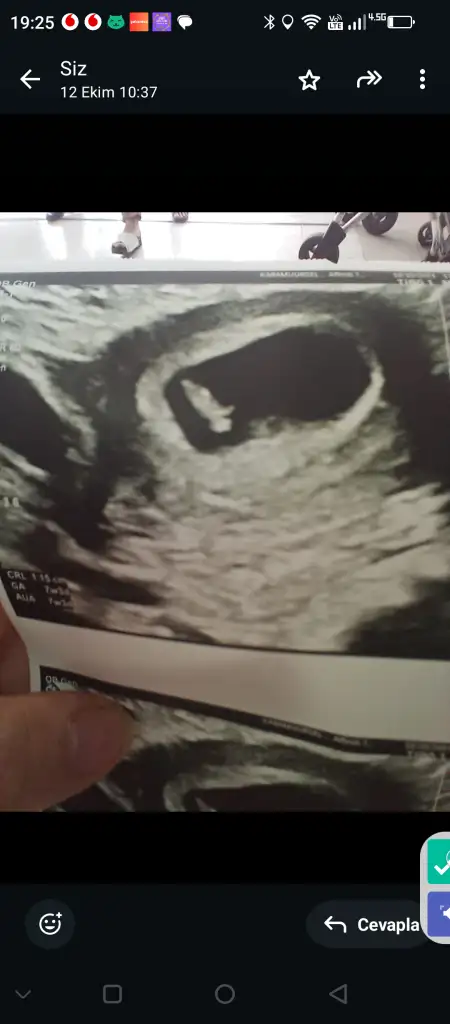

Benim bebişime de bakar mısınız 20 haftalık olacak neredeyse ama önce erkek sonra kıza döndü

Eklentiler

• IMG_1175.webp

IMG_1175.webp

19 KB · Görüntüleme: 38